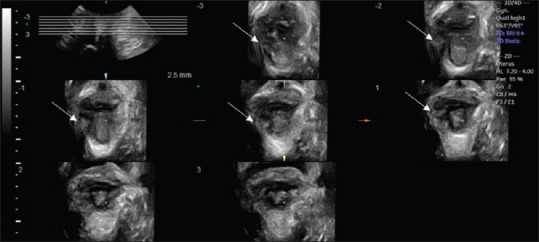

Transperineal 3DUS was performed, with the patient in the lithotomy position, using a convex volumetric transducer with automatic sweep (RAB 4–8 L) of the Voluson E8 Expert apparatus (General Electric, Healthcare, Zipf, Austria). The labia minora was parted, and the transducer was positioned in the vaginal introitus and oriented in a mid-sagittal plane with minimal pressure. Evaluations were performed at rest, maximum Valsalva, and pelvic floor muscle contraction (PFMC). Tomographic ultrasound imaging (TUI) was performed on 3D volumes obtained at PFMC at 2.5-mm slice intervals above the plane of minimal hiatal dimensions [Figure 1].

Figure 1.

Transperineal three-dimensional ultrasound using tomographic ultrasound imaging for pelvic floor muscles in contraction performed before physiotherapeutic treatment shows a complete right-sided trauma (left on image, indicated by the white arrow) visible in all tomographic slices 2.5 mm above the plane of minimal dimensions